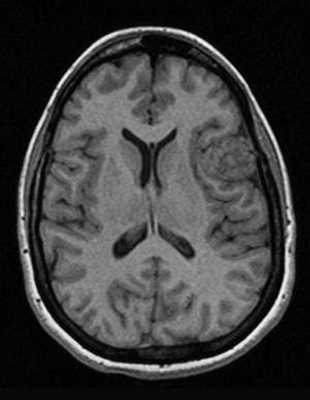

Как же узнать, есть ли на снимках признаки болезни? Самое главное - запомнить, как выглядит головной мозг здорового человека. Врач, изучая снимки пациентов, постоянно сравнивает их с нормальными снимками, хранящимися у него в голове. Чтобы понять, как это происходит - посмотрите на снимки внизу:

Перед вами - два снимка, сделанных в одном режиме. Снимок снизу - норма. Какое заболевание, в таком случае, есть на верхнем снимке? Чтобы понять это, нужно сравнить эти изображения. Явно видно отличие - на верхнем снимке в правой части головного мозга есть новообразование. Разница еще заметнее, если сравнить левую и правую части того же снимка.

Отметим его красной окружностью. Визуально оно представляет собой узел, неоднородный по окраске и отличающийся от серого и белого вещества головного мозга. В таких случаях, чтобы точно определить границы опухоли и определить её тип исследование повторяют с контрастом. Введение контрастного препарата в кровь через локтевую вену приводит к накоплению контрастного вещества в тканях опухоли - нормальные здоровые ткани его практически не накапливают. И мы получаем следующую картину, показанную на рисунке справа. Яркая окраска опухоли соответствует накопленному контрасту - теперь можно не только сказать, где опухоль, но и примерно определить, что это доброкачественная опухоль, так как она имеет четкие границы (злокачественные опухоли прорастают окружающие ткани, из-за чего границы будут размытыми и не такими четкими).

Таким образом расшифровка результатов МРТ головного мозга проводится путем сравнения полученных снимков с нормой. При отсутствии отличий можно говорить о том, что пациент, чьи снимки исследует врач, скорее всего здоров. Сравнивается все - форма, размеры анатомических структур, локализация, симметричность, количество спинномозговой жидкости в полостях головного мозга, и множество других параметров. Каждое заболевание, будь то инсульт или рассеянный склероз, имеет свои характерные признаки.